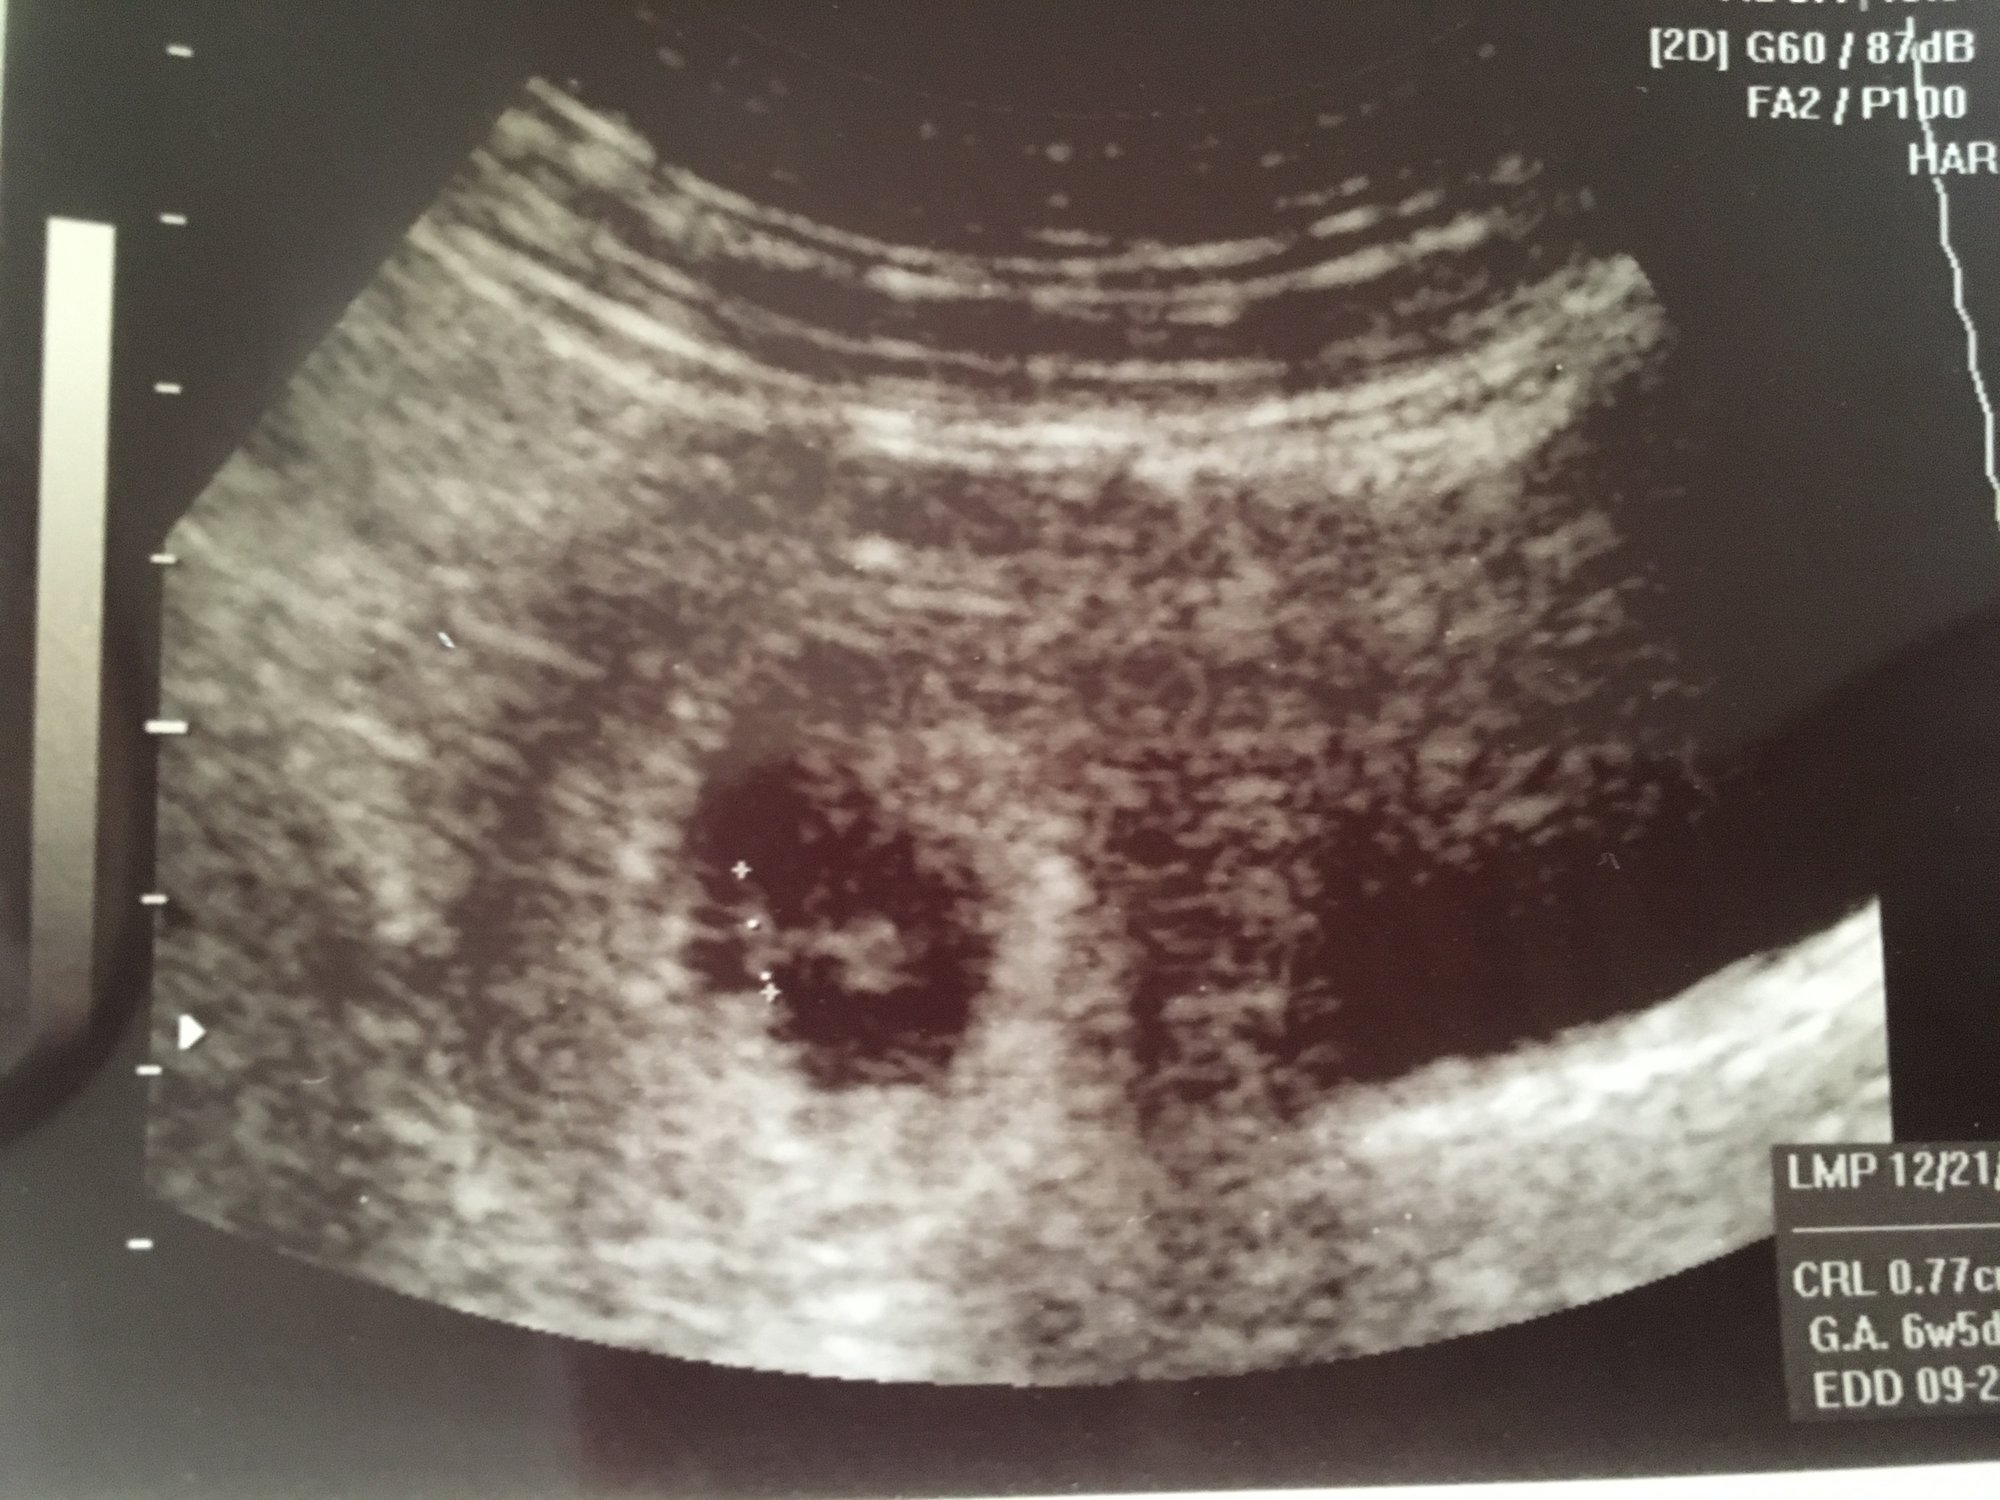

• Hello ladies, my 6w 4d ultrasound pic is super blurry awful, so I haven’t posted here. I plan to after the next one. BUT, I just got the ultrasound results, I had to go in because of some bleeding which has since stopped.

After the ultrasound my ob called to say “you’re not out of the woods yet for miscarriage, but it isn’t ectopic”.  :|

Looks to me like the little minnow is measuring good and had a decent heartrate? I’m focuing on that and ignoring the hematoma bit... I see my ob on the 14th.